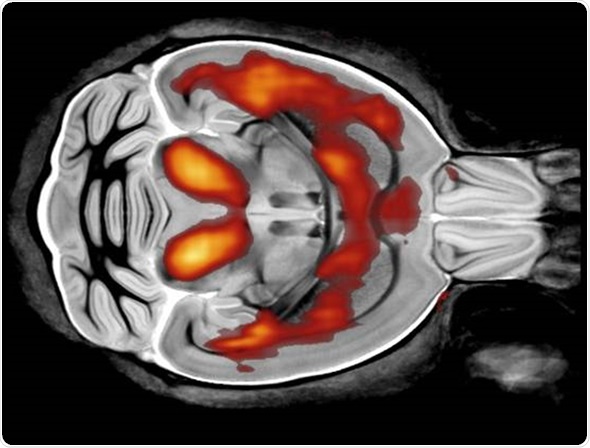

Each modality looks at tissue in a different way. For example, MRI has very good soft tissue contrast and there is a number of parameters that are associated with different pathologies.

For example, there are T1 and T2 changes in cancer and neurodegenerative diseases, whereas, with a modality like CT, there's less soft tissue contrast and it would be used more to look at things like bone structure. It uses a different type of contrast and produces images through a different physical mechanism.

The MRI has a very good soft tissue contrast. The parameters that I generally look at using MRI are called T1 and T2. These vary in different tissues, obviously, but also across different pathologies. MRI provides very high sensitivity to these pathologies, which can't be seen using other modalities.